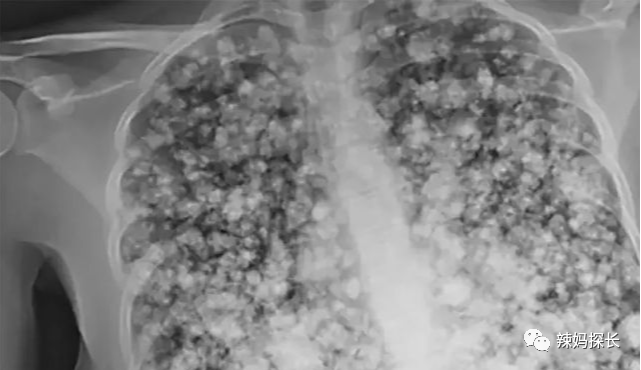

一位17岁的高中生,双肺竟变成“爆米花”,罪魁祸首就是很多人都听说过甚至用过的东西——电子烟。

这位少年,连续5个月使用电子烟,后来因为经常咳嗽、呼吸急促等原因入院检查,才发现了“爆米花肺”。由于他呼吸困难,医生不得不给他插满了管子进行治疗。